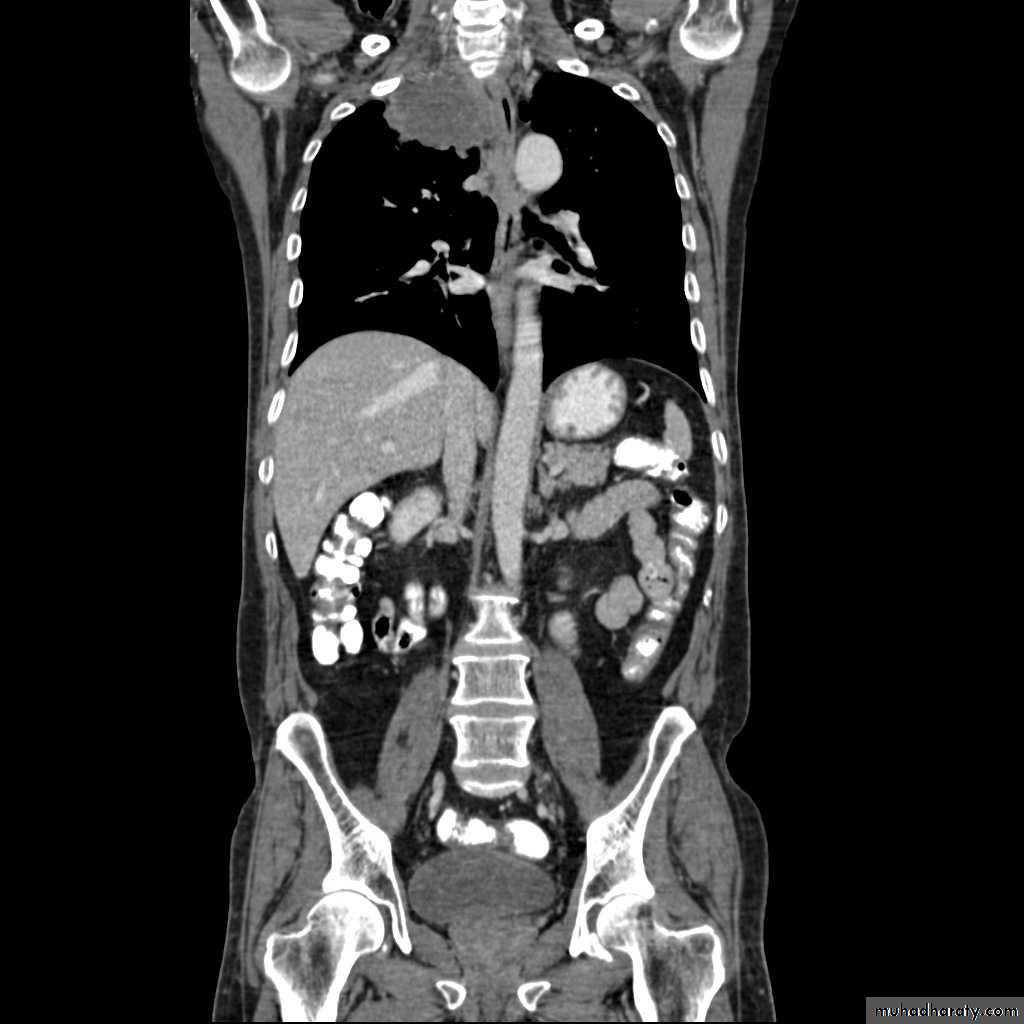

Secondary lung tumor

Pulmonary metastases are common and the result of metastatic spread to the lungs from a variety of tumors and can spread via blood or lymphatics.1.Cannonball metastases refer to large well circumscribed, round multiple opacities like cannonballs

2.lymphangitis carcinomatosis , is the term given to tumor spread through the lymphatics of the lung , and is most commonly seen secondary to adenocarcinoma Unfortunately up to a quarter of patients with subsequently established lymphangitic carcinomatosis have normal chest x-rays . When abnormal the most common finding is of a reticulonodular pattern, with thickening of the interlobular septae which may resemble Kerley B lines + /- pleural effusion .

3.innumerable small metastases (miliary pattern).